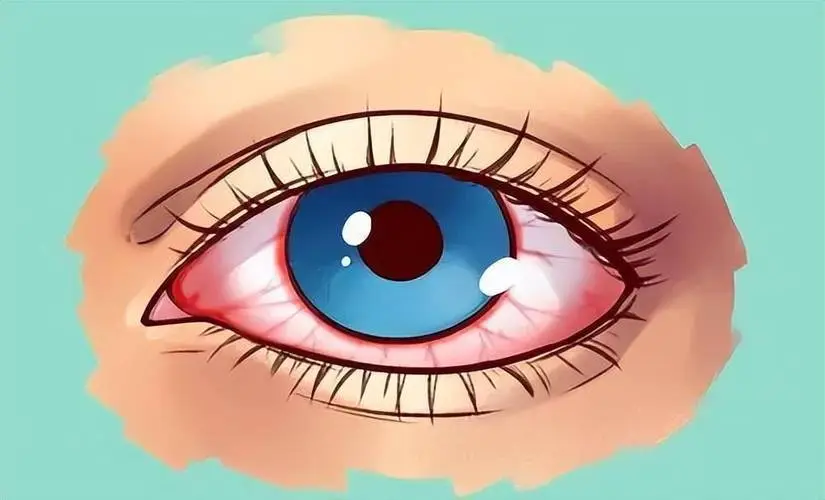

许多朋友在生活中可能会发现自己的白眼球会有充血的情况,一般出现这样的情况,因素是有很多的。睡眠不足,长时间使用眼睛,一些眼科疾病等等都有可能会导致这样的情况出现。

1.患上了急性结膜炎,急性结膜炎为细菌、病毒感染所引起的一种常见的流行性眼病,传染性强。2.患上了急性虹膜睫状体炎,可能与自身免疫性疾病如风湿以及结核、梅毒、病毒感染等有关。

3.患上了角膜炎,角膜炎大多数角膜炎是由外来感染引起的。轻微的角膜外伤常是感染的诱因,常见的致病原为细菌、真菌、病毒等。

4.患上了急性闭角型青光眼,发病原因较为复杂,女性为男性的2~4倍,多发生于中老年妇女,为双眼疾病,与遗传有一定的关系。

5.可能是球结膜下出血,球结膜下出血大都因高血压动脉硬化,凝血功能不良及局部血管炎症或脆性增加,用力屏气或外伤所致。